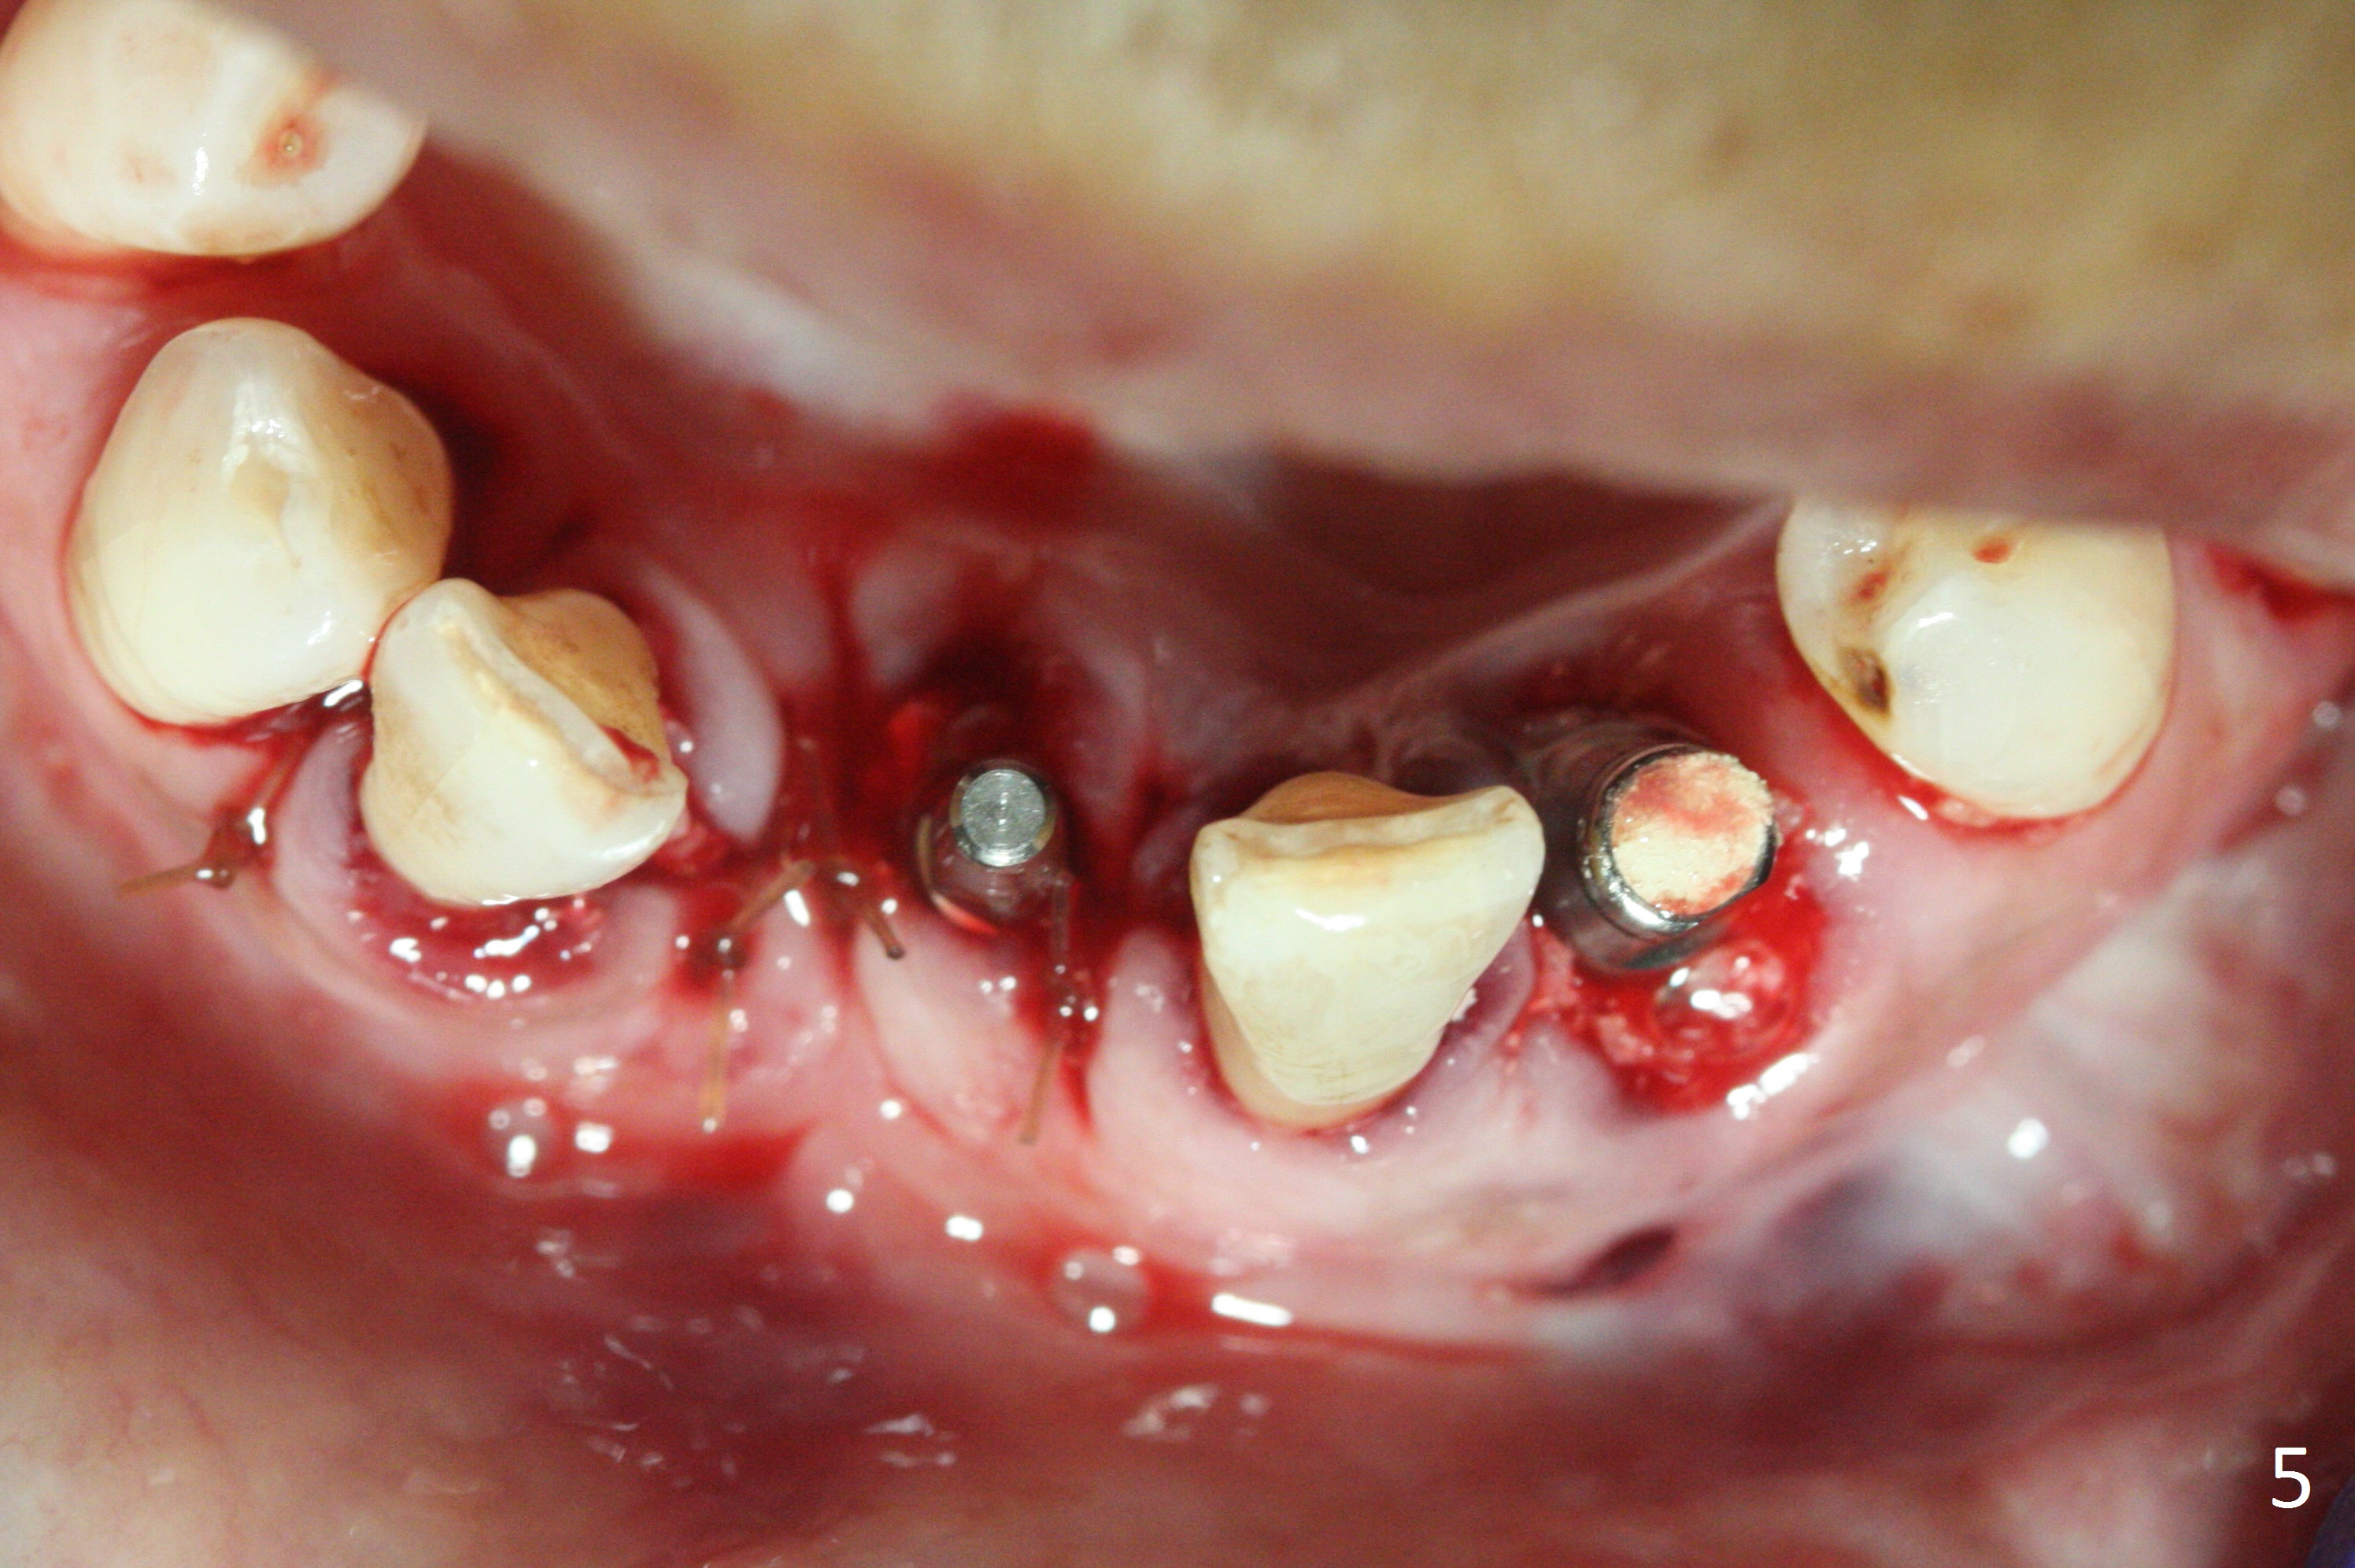

The depth of the osteotomy at #22 is 2-3 mm more than the expected implant length (Fig.2 with 2.7 mm drill in place). The implant at #22 (3.8x18 mm with insertion torque more than 50 Ncm) has clearance from the Incisive Canal and Mental Loop (Fig.3 red dashed line). Allograft with Osteogen is placed around the implants (Fig.4 *) in addition to Osteogen plug (cut in a thin layer) placed against the buccal wall of the socket at #22 (potential leakage). After suturing (Fig.5) and provisional cementation (Fig.6), periodontal dressing is applied (Fig.7). The implants seem to be ready for impression 4 months postop (Fig.8).